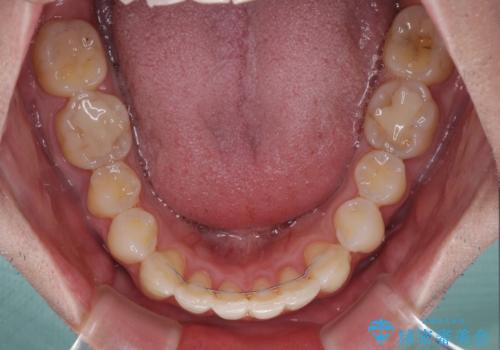

ディープバイトと叢生 インビザラインによる矯正治療

ディープバイトもデコボコも改善され、気になっていた銀歯もセラミックとなり、患者様には大変満足していただきました。

上下ともに叢生が認められたため、親知らずすべてを抜歯し、歯列全体を後方へ移動させることで歯列を整えることとしました。

上顎奥歯の銀歯も気になっていたので、矯正治療の途中でセラミッククラウンへ変更し、その後歯列を仕上げていくこととしました。